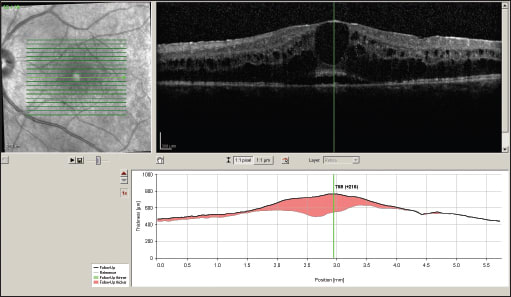

After the risks and benefits of systemic immunomodulatory and local therapy were explained, the patient elected to have Retisert placement in her left eye. Visual acuity improved to 20/80 four weeks after treatment. Eight weeks after treatment, acuity was 20/60.

Two months after implant placement OS, the right eye was implanted. VA was 20/200 OD and 20/60 OS at that time. Four weeks after implantation OD, VA improved to 20/60 OD, and then to 20/40 OD eight weeks later (Figure 3). OCT nine months later showed dramatic resolution of CME (Figure 4). The pre-existing PSC cataract progressed. Phacoemulsification surgery with in-the-bag IOL implantation was performed OS 11 months after Retisert implantation in that eye. Vision improved from 20/80 to 20/50 after the surgery.

Figure 3. OCT of the left eye (upper image) and right eye (lower image) after Retisert placement.